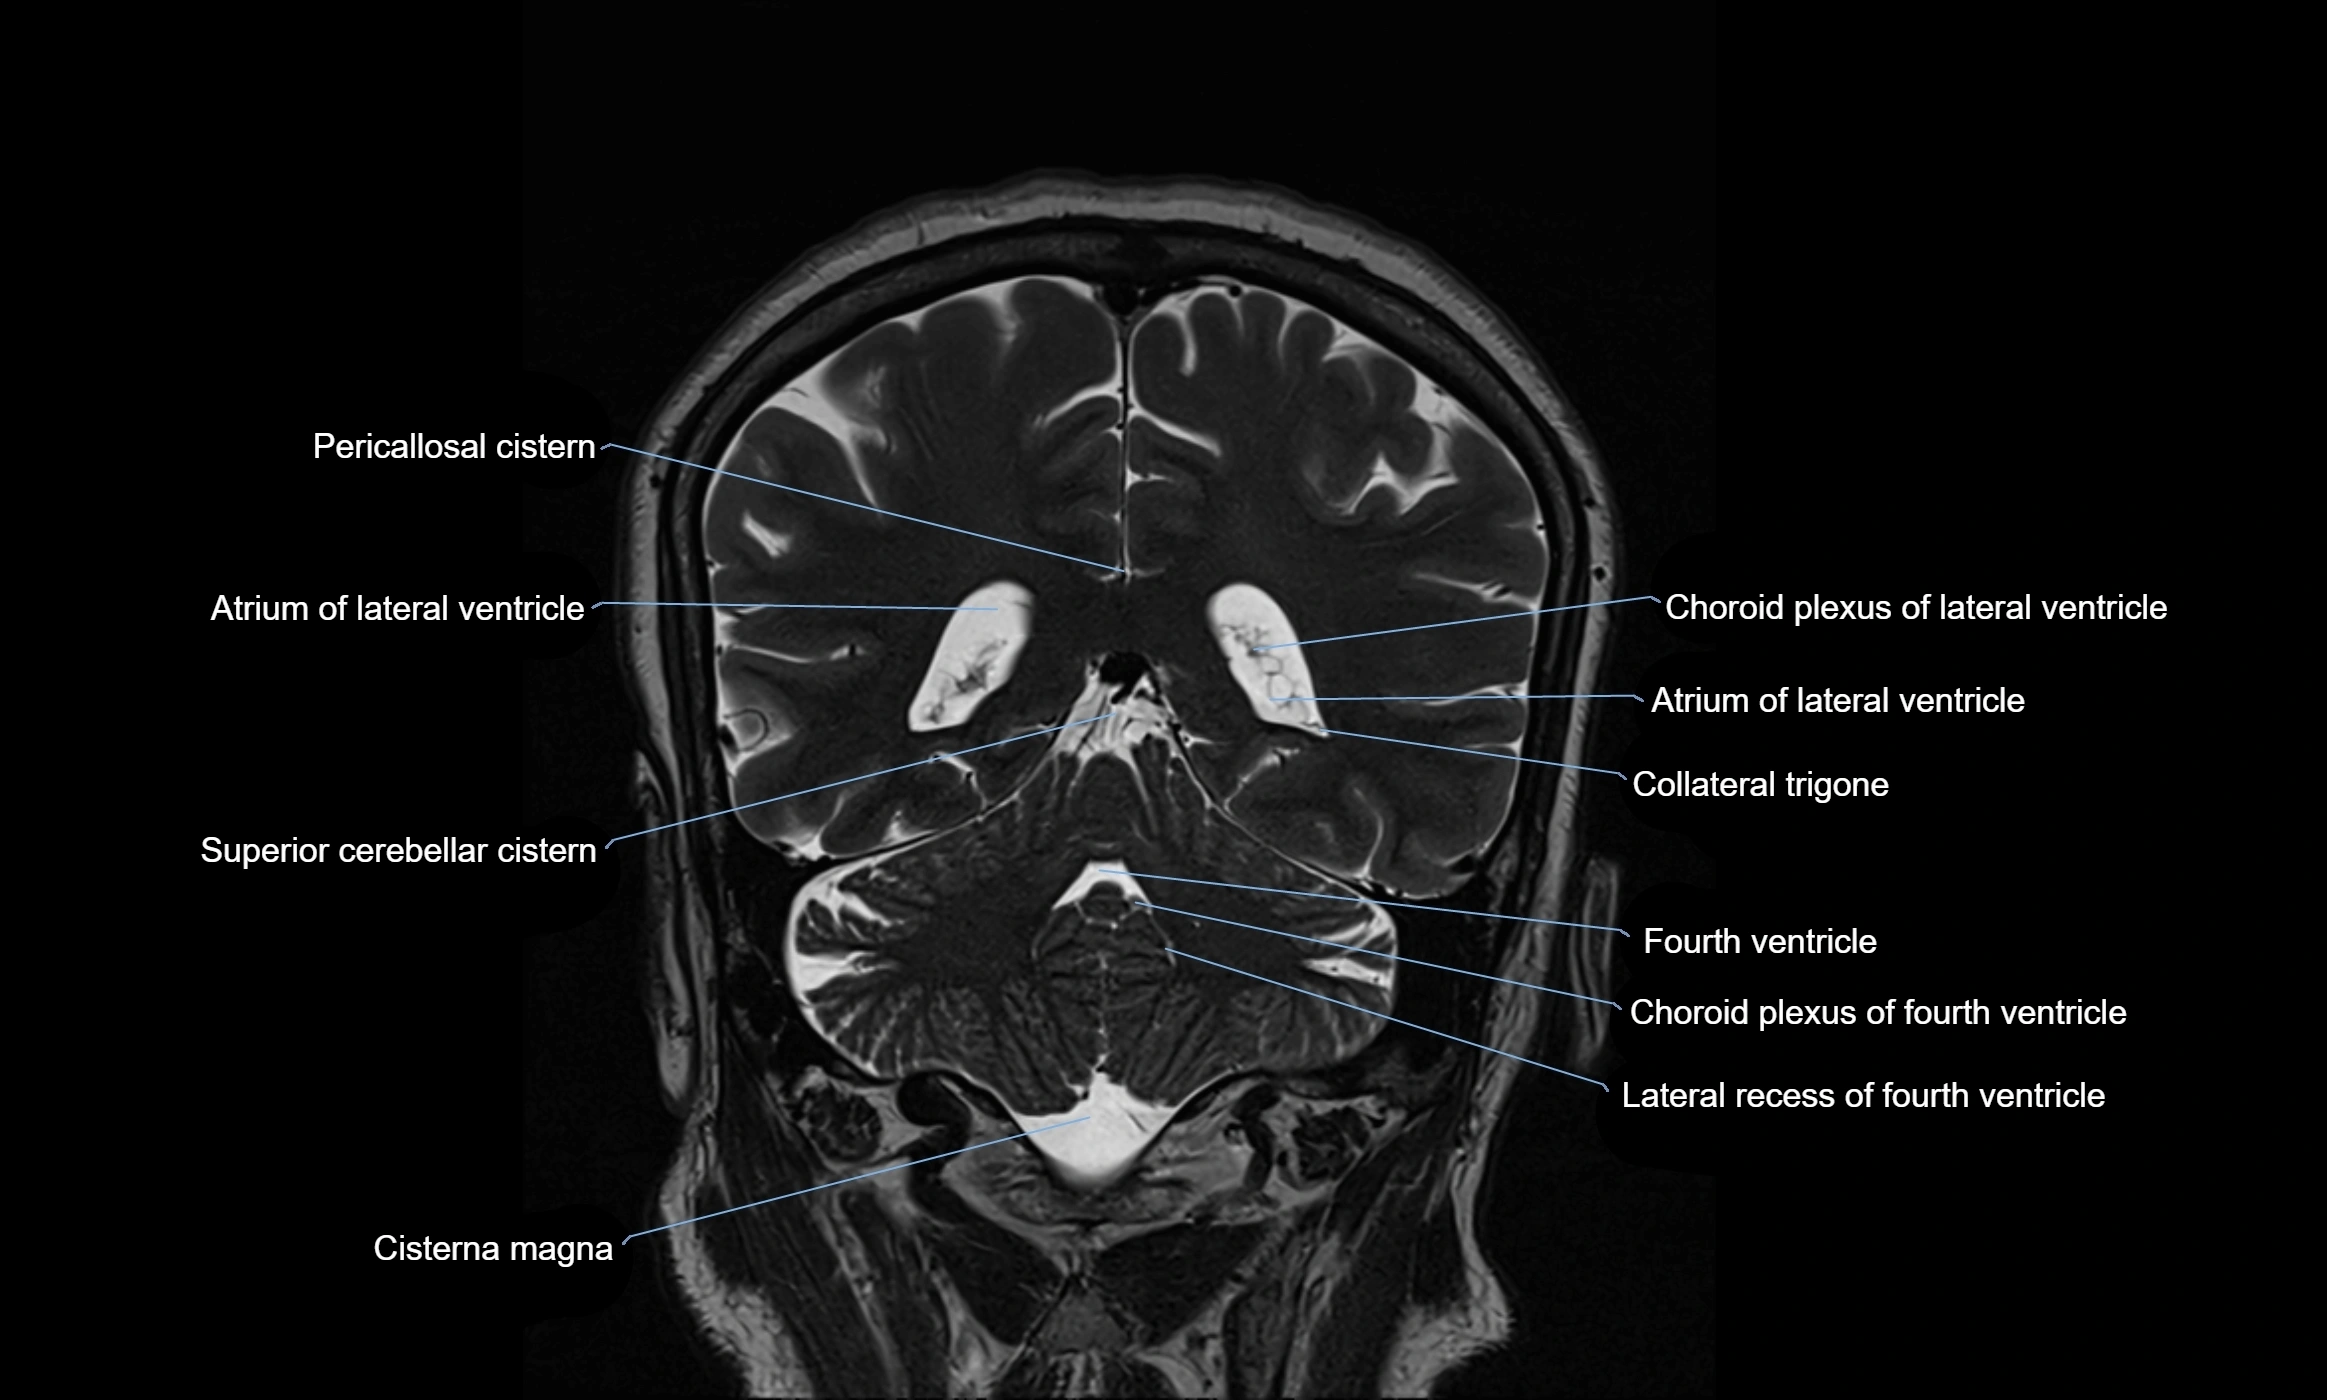

CT image

image